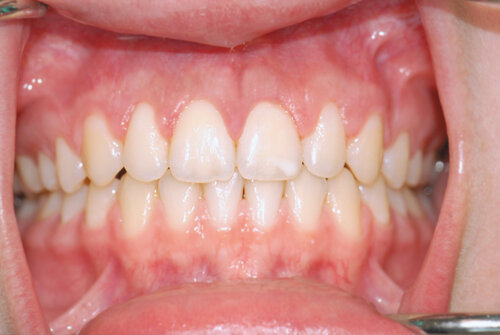

Before

Note the exposed root surfaces (recession) of the upper teeth.

After

We performed a simple gum grafting procedure to reposition the gum tissue and cover the roots. This helps decrease the chances of root cavities and sensitivity while providing significant aesthetic improvement.